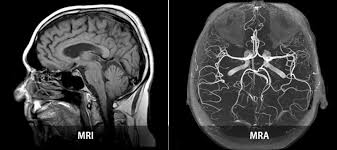

- MRI (자기공명영상): 강한 자기장과 라디오파를 사용해 내부 구조(근육, 뇌, 장기 등)의 단면 영상을 생성합니다. 방사선 노출 없이 해상도가 뛰어나 종양, 염증, 디스크 병변 진단에 탁월합니다 :contentReference[oaicite:1]{index=1}.

- MRA (자기공명혈관조영술): MRI 원리를 적용해 **혈관 내부 구조와 혈류 흐름**을 3D 영상으로 확인하는 검사입니다. 동맥류, 혈관 협착·폐쇄·혈전 등의 진단에 사용됩니다 :contentReference[oaicite:2]{index=2}.

즉, MRI는 **조직 중심** 진단, MRA는 **혈관 상태와 혈류 흐름**을 중점으로 합니다 :contentReference[oaicite:3]{index=3}.

- 두 검사 모두 MRI 장비로 촬영하며, 검사대에 눕고 튜브 내부로 들어가는 방식은 동일합니다.